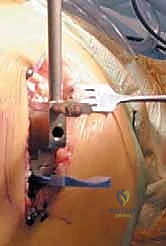

صورة طبية: استبدال مفصل الركبة الجزئي (UKA): دليل شامل لمرضى خشونة الركبة الداخلية مع الأستاذ الدكتور محمد هطيف